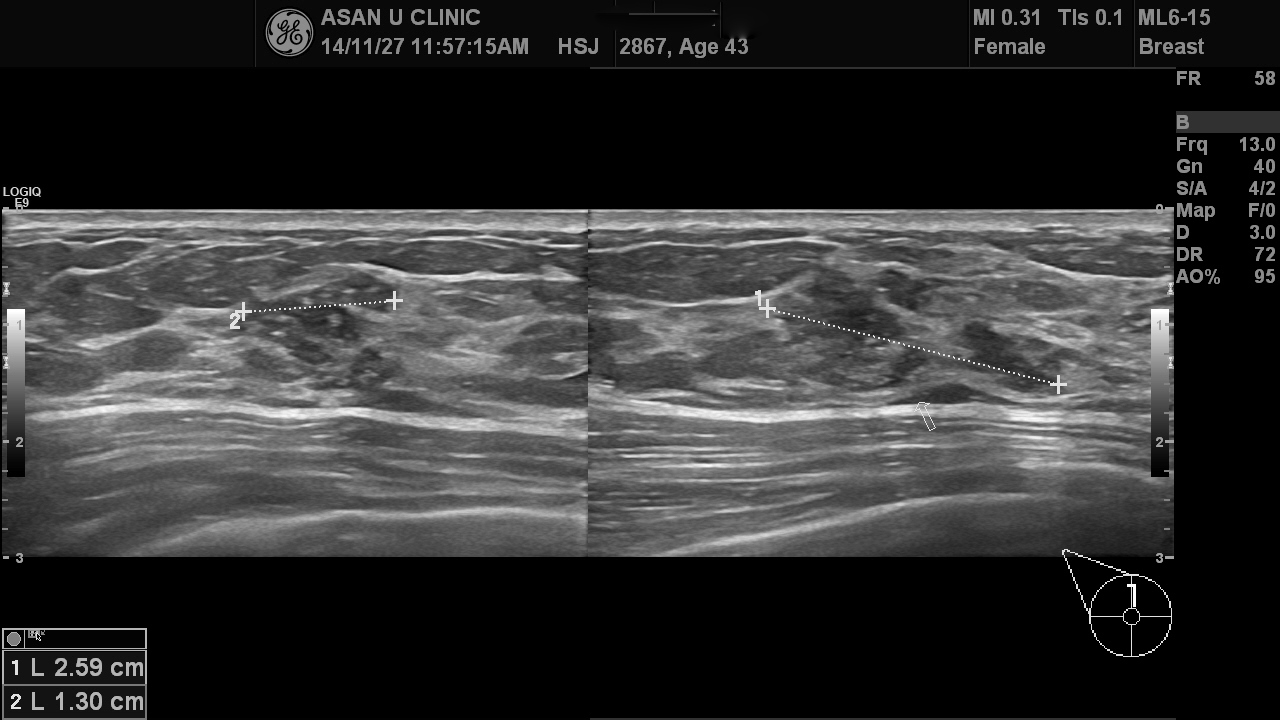

건강검진상 이상소견으로 내원하신  44세 여성분입니다.

미세석회화와 불규칙 유관확장이 있는 오른쪽 유방의 상내측의 결절이었고

조직검사로 미세침윤성 유관암이 진단되셨습니다.